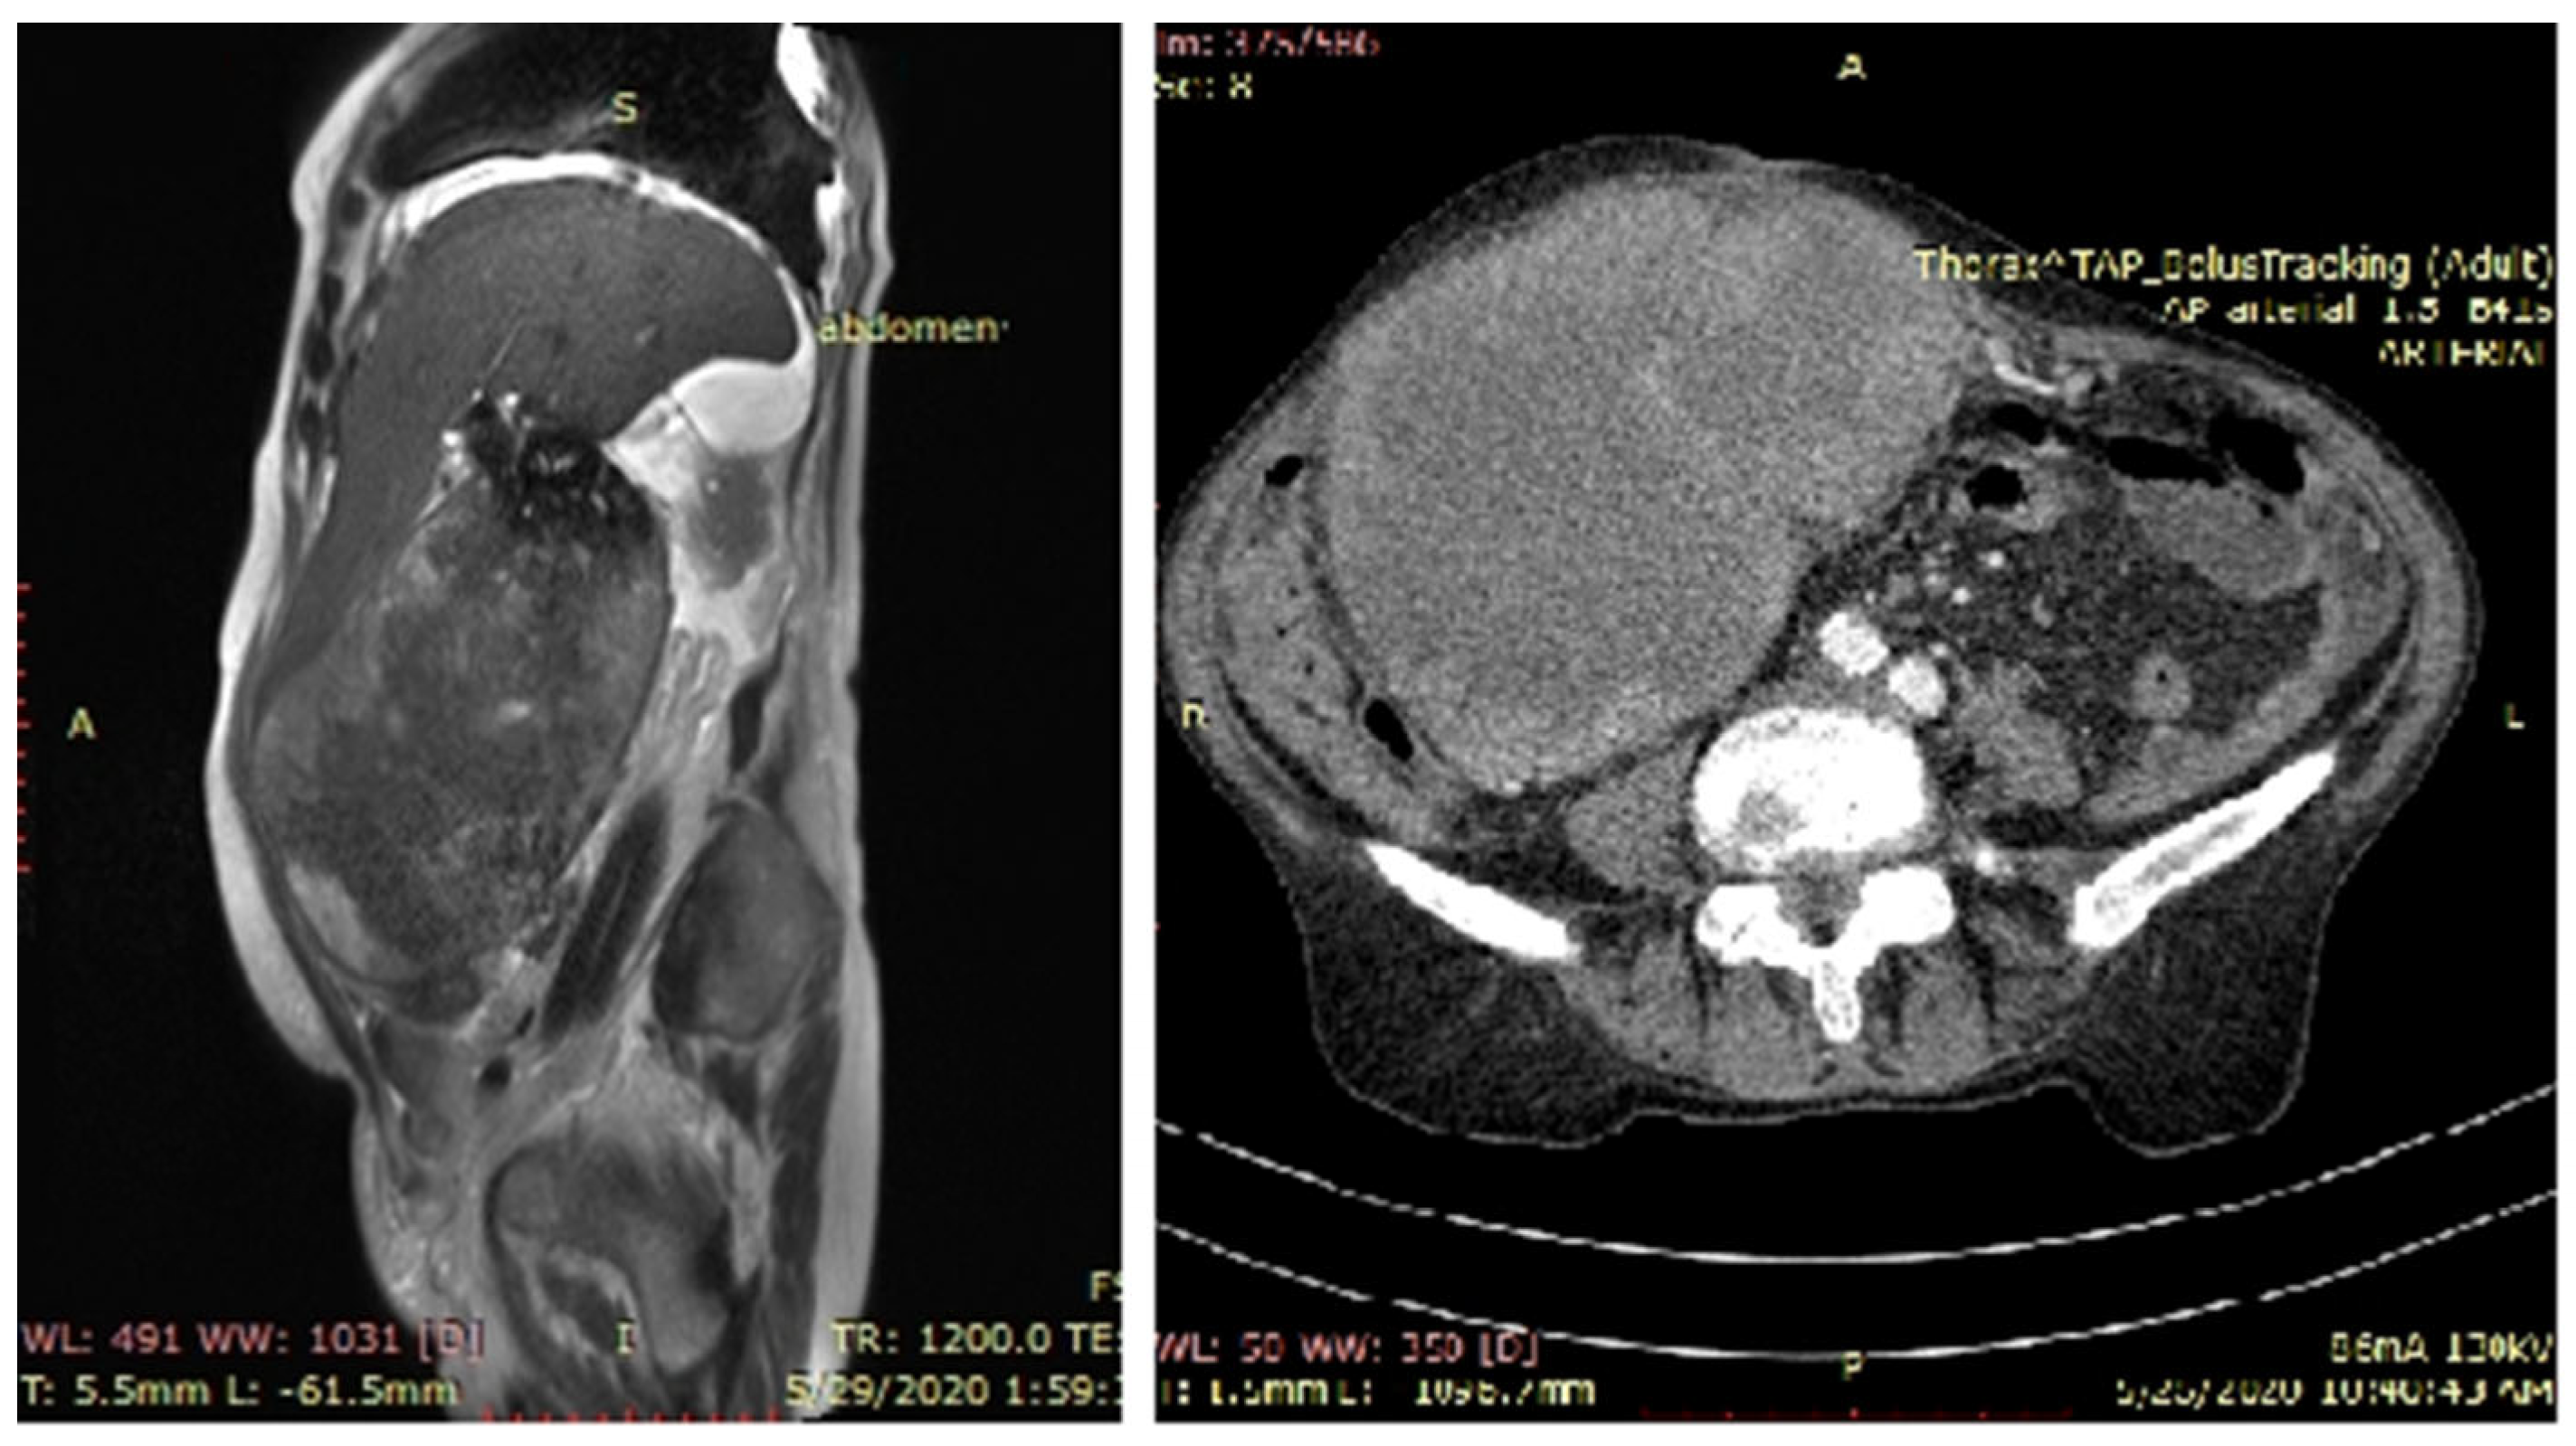

MRI highlighted an abdominal tumor located in the right hypochondrium and right abdominal flank with liver invasion (segment V). At the lower pole, the tumor wall was discontinuous. Intraperitoneal tumor extension was detected over a length of approximately 25 mm, with the invasion of the small bowel and omentum at this level. The tumor had a mixed appearance: solid-wall, gadolinophilic, with a maximum thickness of 35 mm and an inhomogeneous central liquid portion. Multiple stones, some of them with a diameter of 18 mm, were visible in the lower part of the tumor, but most agglutinated in the upper part, with dimensions varying between 5 and 30 mm. There were no lymph nodes and no metastasis. The common bile duct appeared with a normal caliber, alithiasic, and pushed antero-superior by the tumor mass, with no sign of invasion. This imaging result is characteristic of primitive gallbladder cancer (Figure 1). A cT3N0M0 stage was established under the limitations of the imaging evaluation difficulties regarding the large volume of the tumor, which made it hard to evaluate its relationships with the neighboring structures. CEA and CA 19.9 levels were within normal ranges.

Figure 1.

MRI (left) and CT (right) images, sagittal section and cross-section. A large subhepatic tumor mass occupied the entire flank and right hypochondrium, with the blurring of the demarcation line from the colon, duodenum, and jejunum, which appeared invaded by the tumor mass.